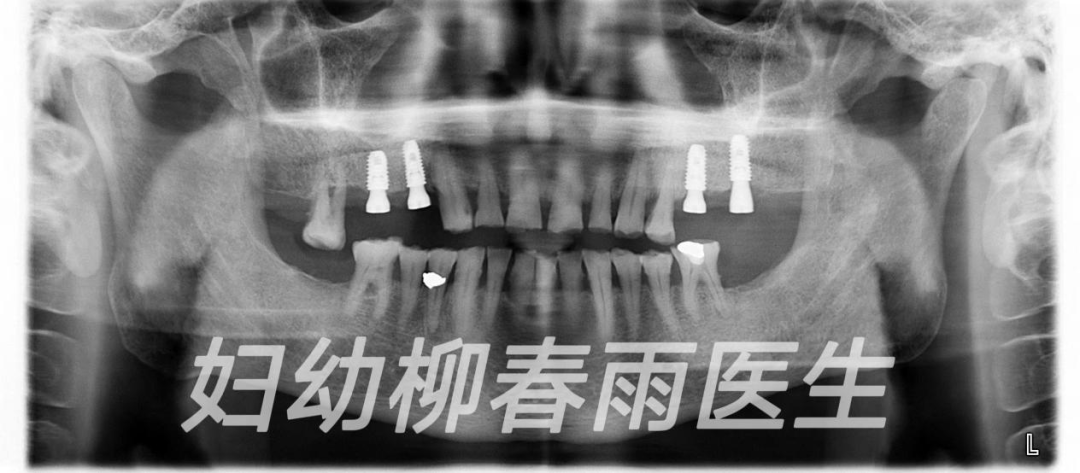

首先需要抽血化驗評估患者的身體健康狀況是否適合種植牙,拍攝CT 檢查患者口腔內(nèi)的具體情況,包括牙周情況、牙槽骨情況、對合牙情況、鄰牙情況等,醫(yī)生會通過拍攝的CT測量牙槽骨的高度、寬度、了解口內(nèi)情況,設(shè)計種植手術(shù)方案。